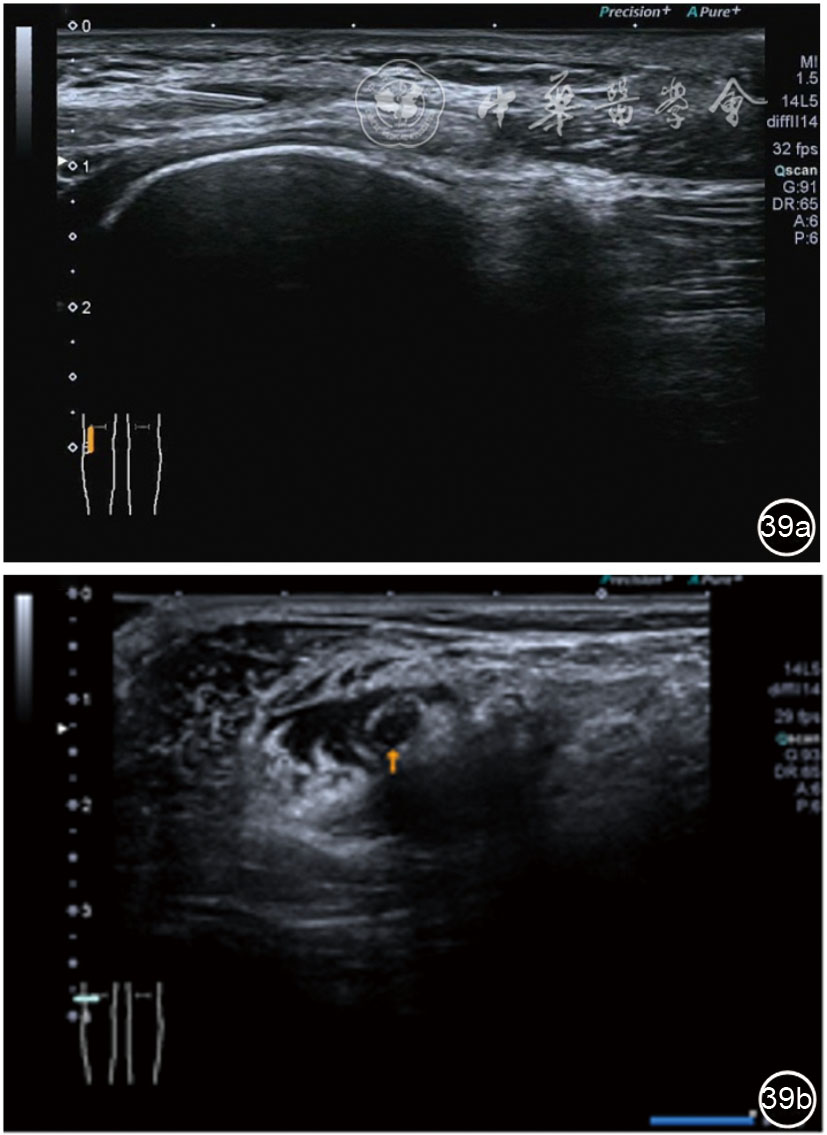

3.膝关节内局部治疗。随着病情发展,静态结构失衡,膝关节内部结构发生变化,会出现软骨损伤、脱落,关节间隙变窄,内外间隙不等,骨赘形成等。膝关节内局部治疗包括关节内症状性骨赘剥离、玻璃酸钠及PRP注射等。(1)膝关节内症状性骨赘针刀剥离松解治疗。由于软骨缺损或者力平衡失调,在关节内脱落软骨区会出现骨赘。部分骨赘引起疼痛,或者与髌骨撞击出现临床症状需要治疗。针刀剥离目的不是去除骨赘,而是剥离松解,缓解或者消除疼痛。以股骨外髁骨赘为例。患者平卧位,膝关节屈曲100°~120°。一般选用10 MHz超声探头,穿刺区域常规消毒,探头涂抹耦合剂后套入无菌手套碘伏消毒或使用无菌耦合剂。将探头置于患者皮肤表面,短轴扫查,显示关节面与骨赘,选用25G注射针,抽吸1%利多卡因3 ml于骨赘周围进行分层麻醉。选用直径1 mm的Ⅰ型2号针刀,在超声引导下从外侧向内侧到达骨赘,反复剥离,一般5~8刀后拔出针刀结束治疗(图18),局部压迫5分钟,无菌敷料覆盖。(2)膝关节髌上囊积液治疗。髌上囊积液在膝关节骨关节炎比较常见,尽管积液量可能很大,但通过软组织松解治疗后,大部分患者积液会减少或者消失。所以积液的治疗可以放在后面处理。超声引导下抽出积液,药物注射是常用的治疗方法。膝关节炎积液的治疗通常包括关节内皮质类固醇激素或者臭氧注射。如果慢性以滑膜丛型增生为主,针刀有限切割增生滑膜加药物注射可提高疗效。①髌上囊积液抽吸加臭氧注射治疗。患者平卧位,膝关节屈曲30°~60°,膝下垫一软枕。选用10 MHz超声探头,治疗前消毒准备同骨赘针刀剥离松解治疗。将探头置于患者皮肤表面,短轴扫查,找到积液最多处,应用22G针头,直接穿刺进入髌上囊抽出液体,然后根据髌上囊大小制备35 μg/L的15~20 ml臭氧注入髌上囊内拔出针头(图19),局部压迫2分钟,无菌敷料覆盖。②髌上囊慢性滑膜炎针刀切割松解治疗。患者平卧位,膝关节屈曲30°~60°,膝下垫一软枕。选用10 MHz超声探头,治疗前消毒准备同骨赘针刀剥离松解治疗。将探头置于患者皮肤表面,长轴或短轴扫查,找到积液最多处,用一次性5 ml注射器抽吸1%利多卡因3 ml于髌上囊进行分层注射麻醉,囊内也要注射适量麻药,尽量抽出积液。选用直径1 mm的Ⅰ型2号针刀,长轴扫查从近端向远端,短轴扫查从外侧向内侧,在超声引导下进入囊肿内对内壁及增生滑膜的不同方向、角度进行反复切割(图20),一般2~3分钟拔出针刀,然后囊内注射1%利多卡因3 ml+曲安奈德15 mg,结束治疗,局部压迫5分钟,无菌敷料覆盖。(3)膝关节腔PRP注射治疗。关节腔注射主要是为了修复软骨,如果不是为了治疗积液,不主张应用激素类药物。目前主要的注射药物为玻璃酸钠、PRP。按照传统的注射部位,多为髌上内、外或者髌下内、外注射点,但是超声不能观察到注射针的位置,药物也不能很好到达软骨损伤的部位,效果受到影响(图21)。膝关节软骨损伤的主要部位在髌股关节的股骨髁,超声可以很好地显示这一部位,并能显示软骨变薄。因此,由这个路径平面内进针注射,可以很好显示穿刺针的路径与位置。以注射PRP为例。患者平卧位,膝关节屈曲100°~120°,选用10 MHz超声探头,治疗前消毒准备同骨赘针刀剥离松解治疗。将探头置于患者皮肤表面,短轴扫查显示关节面,应用25G注射针头,抽吸1%利多卡因2 ml由内侧进针进行分层麻醉直达关节软骨面。制备4.5 ml PRP,直接注射到关节面,液体顺关节面分布,注射完毕拔出针头(图22)。局部压迫2分钟,无菌敷料覆盖。(4)髌骨软化超声影像融合技术下PRP注射治疗。髌骨软化是指髌骨关节面的软骨损伤,软骨下骨囊变,MRI能够明确诊断,但是超声不能显示。应用超声与MRI的影像融合技术,依据MRI明确注射部位,在超声引导下可将药物精准注射到软骨损伤的部位。患者平卧位,膝关节屈曲30°,下面垫一软枕。一般选用10 MHz超声探头,治疗前消毒准备同骨赘针刀剥离松解治疗。将MRI的原始图像数据导入超声设备中,进行手动影像融合,完全融合后,确定穿刺靶点,以MRI图像为目标,以超声图像为实时引导进行穿刺,到达目标后,注射提前制取的PRP 3 ml(图23),注射完毕拔出针头,局部压迫3分钟,创可贴覆盖。

图23 髌骨软化MRI与超声影像融合技术下富血小板血浆注射治疗图像